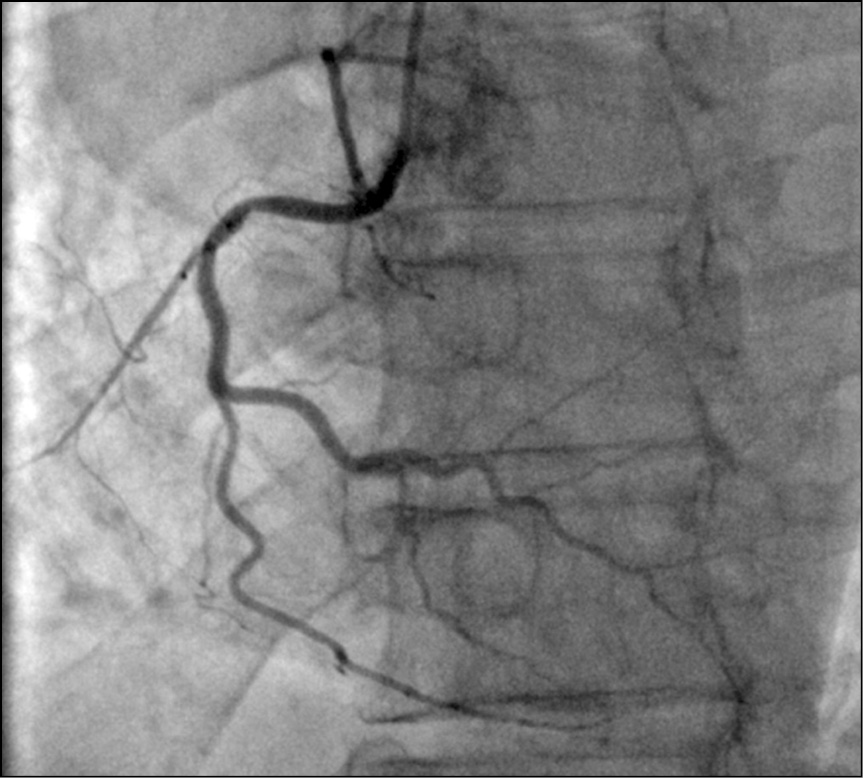

Рис. 4. Тот же пациент: селективная коронарография правой коронарной артерии.

Fig. 4. The same patient: selective coronary angiography of the right coronary artery.